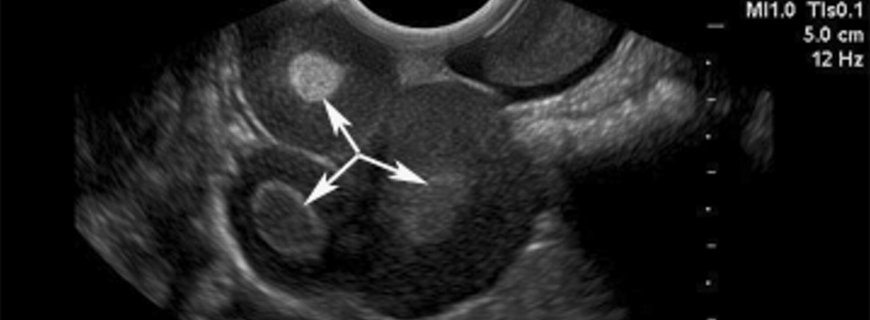

Yumurtalıkta gelişen iyi ve kötü huylu tümöral kitleler kadınların %5 ila 7\'sinde görülmektedir. A.B.D’de aşağı yukarı her 70 kadından birinde hayatları boyunca yumurtalık kanseri ortaya çıkmaktadır. Amerikan Kanser Derneği\'ne göre 2006 yılında yaklaşık 20.180 yeni yumurtalık kanseri olgusu görülmüş ve yumurtalık kanserine bağlı 15.310 ölüm ortaya çıkmıştır. Yumurtalık kanserine benzer olarak meme kanseri (kadınlarda en yüksek sıklığa sahip) 10 kat daha sık ortaya çıkmakta ve akciğer kanseri (en yüksek ölüm oranına sahip) 4,5 kat daha fazla ölüme neden olmaktadır. Tanı esnasındaki ortalama yaş 63\'tür.